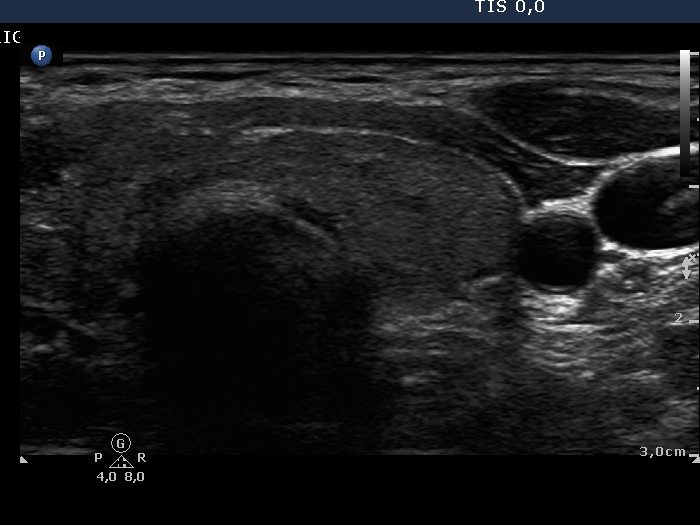

Oxyphilic adenoma - Case 1. |

Clinical data: a 31-year-old woman was referred for an evaluation of newly discovered thyroid nodule. She has been treated for hypothyroidism for 11 years.

Palpation: a firm nodule in the right lobe.

Functional state: euthyroidism on daily 75 microgram levo-tiroxin (TSH 0.99 mIU/L).

Ultrasonography: revealed hypoechogenic nodule with a halo sign and perinodular blood flow in the right thyroid. The left lobe was echonormal with small hypoechogenic lesions. The echogenicity index was 10%.

Cytological report: Hürthle-cell tumor.

Histopathology: disclosed Hürthle-cell adenoma and Hashimoto thyroiditis in the non-nodular part of the lobe.